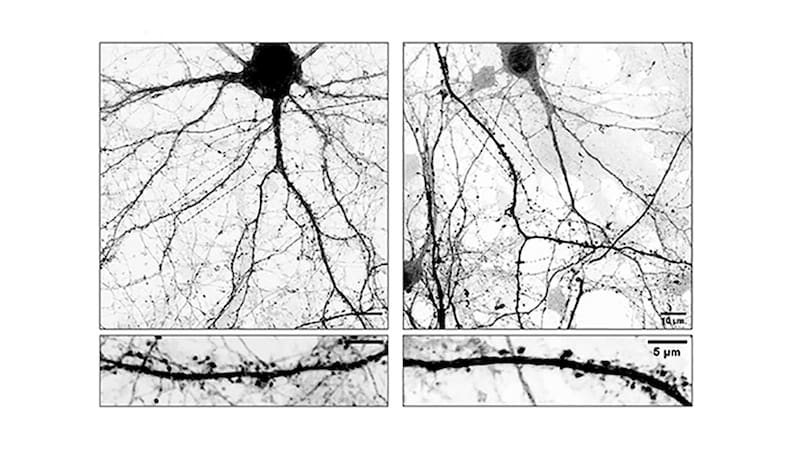

Para llegar a estas conclusiones, los investigadores trabajaron con cultivos de neuronas extraídas de regiones específicas del cerebro de ratones. Utilizaron microscopía de alta resolución y tinciones fluorescentes que les permitieron observar en tiempo real cómo cambiaban las espinas dendríticas —las conexiones entre neuronas— cuando eran expuestas a levodopa.

Lo que vieron fue revelador: el medicamento no solo actuaba sobre la química cerebral, sino que modificaba físicamente la estructura de las células nerviosas.